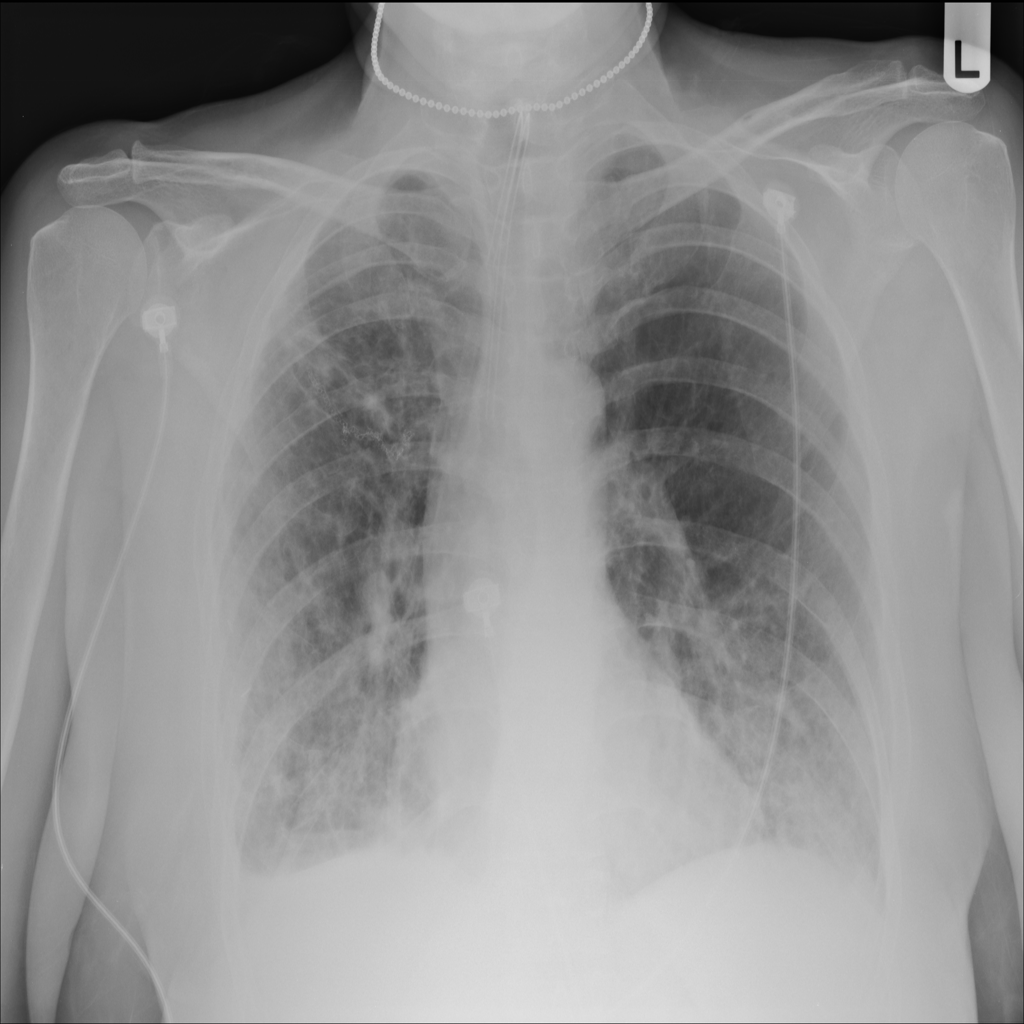

PAT-24D9 · IMG-006Edema

PAT-24D9 · IMG-006

AP